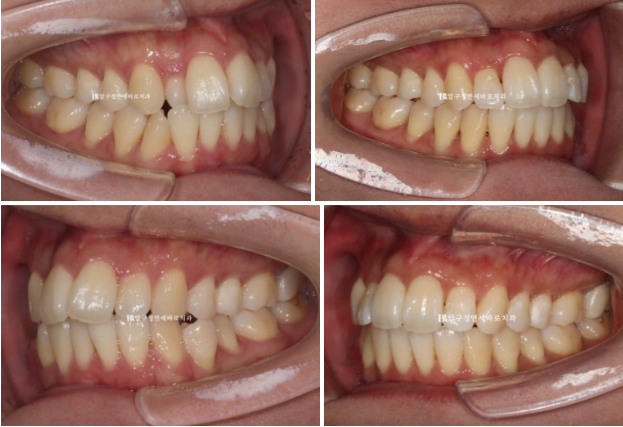

측절치 덧니가 아랫니와 거꾸로 물리는 반대교합을 보입니다.

반대쪽 파란 화살표 부분 작은 어금니 역시 배열에서 튀어나가 있어서 윗니와 거꾸로 물리는 반대교합입니다.

24.02

입천장에 위치하는 측절치

삐뚠 앞니, 작은어금니 덧니 등 앞니 부분교정만으로 해결하기에는 난이도가 있습니다.

치료 시작 후 5개월째의 모습입니다.

24.07

정확히 맞아 떨어지는 중심선

24.02~24.08

거꾸로 물리는 덧니는 해결이 되었고

작은 어금니까지 배열을 마쳤습니다.

내려와 토끼이처럼 보이던 앞니는 높이가 맞아졌고 기울어짐도 치축개선을 통해 좋아졌습니다.

걸려있던 앞니도 제 위치를 찾았습니다.